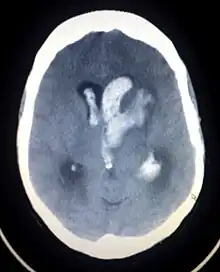

CT-scanning af en hjerneblødning.